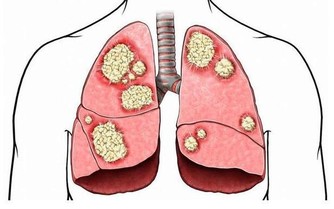

提到尿酸高,很多人第一時間想到的就是痛風,其實,尿酸高不僅會導致痛風,還會引發動脈硬化、糖尿病、腎結石,甚至誘發腎衰竭等等。也就是說,痛風只是高尿酸的所致危害的“冰山一角”。

研究發現:血尿酸水平每增加60維摩/毫升,新發糖尿病風險增加17%;高尿酸患者發生高血壓的風險增加81%,且血尿酸水平每增加60維摩/毫升,高血壓風險增加9%;高尿酸患者的腦卒中發生風險增加22%,腦卒中的死亡風險增加33%。

無症狀高尿酸血症:沉默的殺手!

無症狀的高尿酸血症患者,尿酸水平也已超過正常值,只是由於尿酸鹽沒有沉積到關節或軟組織裡,因此沒有發生痛風關節炎、痛風石或尿酸結石等表現。只有在尿酸鹽在機體組織中沉積下來造成了損害後,患者才會出現痛風。

而且,無論是否出現關節疼痛等痛風症狀,高尿酸血症對人體的損害是一樣的,甚至可以說,正是因為沒有症狀而不會引起注意,反而更具危險性,就像沉默殺手。